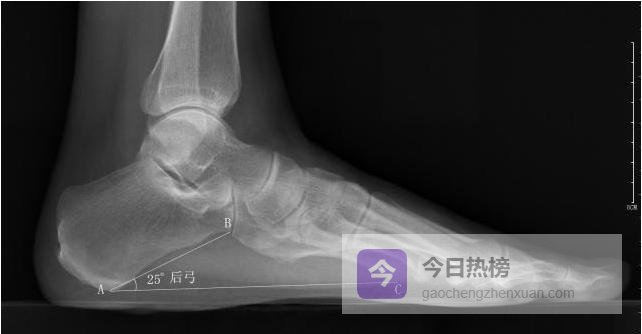

4.2.4 ◆ 后弓角 以跟骨最低点为原点,向跟骰关节最低点与第5跖骨头最低点各引一条水平线, 测量两线夹角。